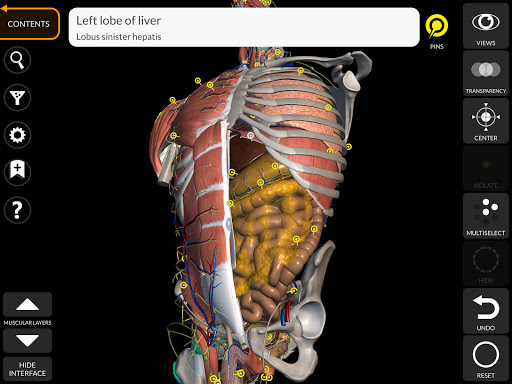

يتيح لك "Anatomy 3D Atlas" دراسة التشريح البشري بطريقة سهلة وتفاعلية.

من خلال واجهة بسيطة وبديهية، من الممكن ملاحظة كل بنية تشريحية من أي زاوية.

تتميز النماذج التشريحية ثلاثية الأبعاد بتفاصيل خاصة ودقة تصل إلى 4K.

يسهل التقسيم حسب المناطق والمناظر المحددة مسبقًا مراقبة ودراسة الأجزاء الفردية أو مجموعات الأنظمة والعلاقات بين الأعضاء المختلفة.

• الجهاز الهضمي

• خيار إخفاء أو عزل نموذج واحد أو نماذج متعددة مختارة

• من خلال تحديد نموذج أو دبوس، يظهر المصطلح التشريحي ذي الصلة